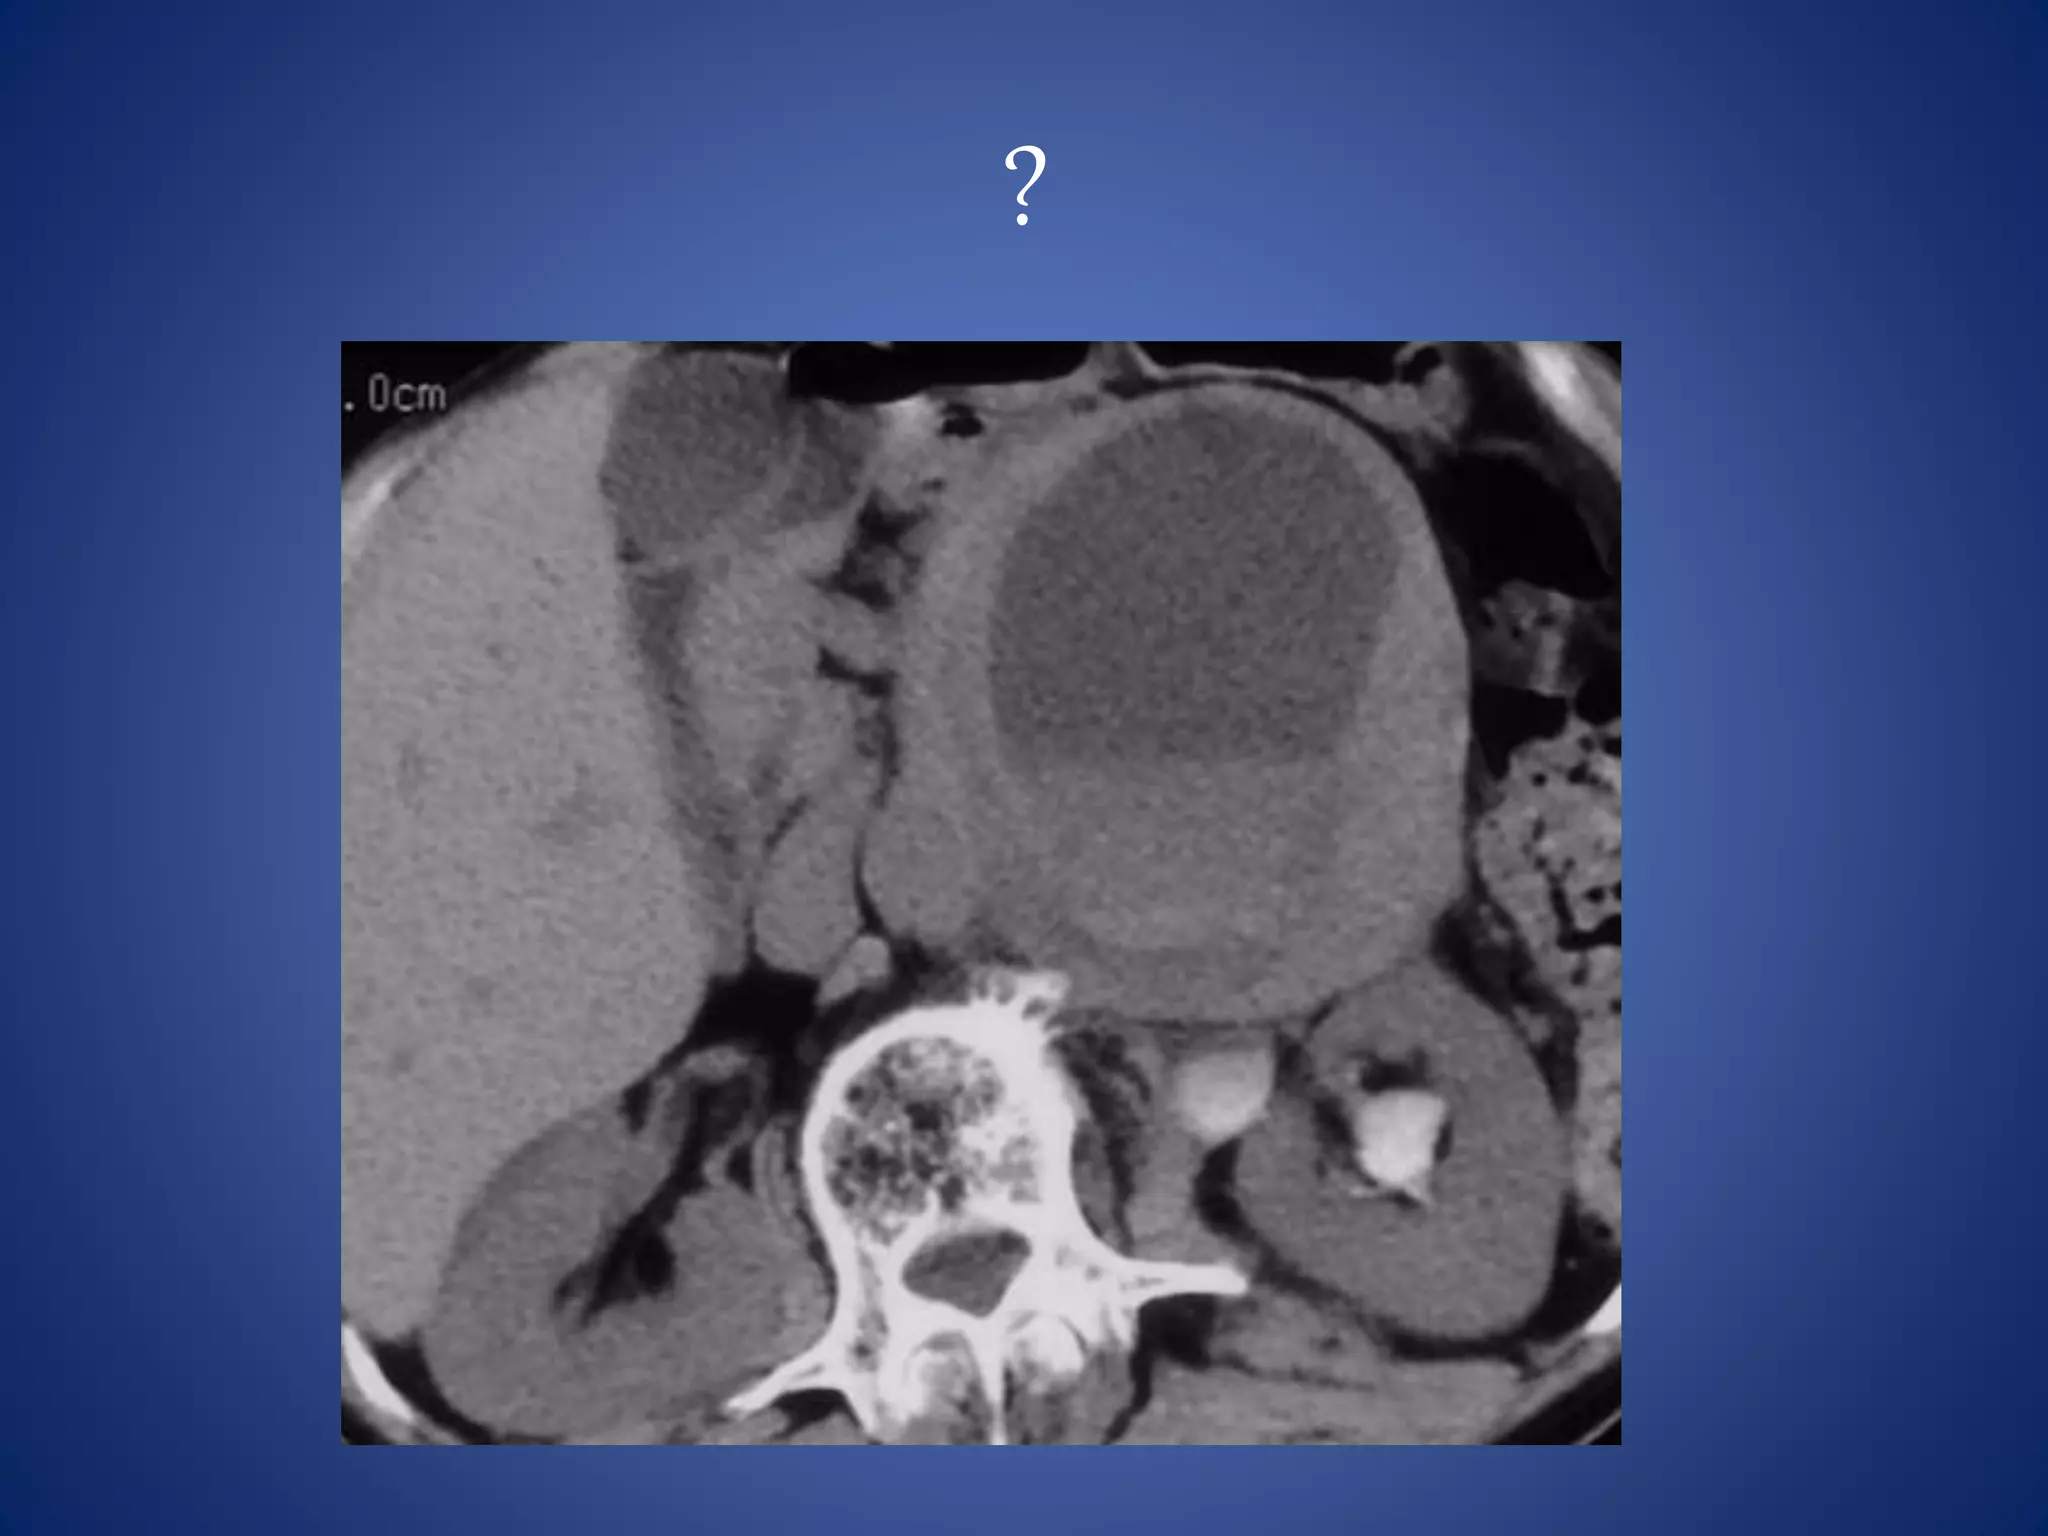

Liposarcoma

Liposarcoma is the most common (33%) primary retroperitoneal

sarcoma.

Liposarcoma is usually large (average diameter, >20 cm) and is a slow-

growing tumor.

It is a predominantly hypoattenuating lesion on CT because of its fat

content. At MR imaging, it follows fat signal.

The appearance of liposarcoma may be similar to that of a lipoma,

but liposarcoma has thicker, irregular, and nodular septa that show

enhancement after contrast material administration.

Lipoma is less common than liposarcoma in the retroperitoneum.

• #11 Well-differentiated liposarcoma in a 58-year-old woman is shown as a large homogeneous fat-containing mass with thick septa (arrows) that show soft tissue attenuation.

• #73 Liposarcoma --- Large retroperitoneal mass predominantly of fatty attenutation with irregular nodular septations The appearance of liposarcoma may be similar to that of a lipoma, but liposarcoma has thicker, irregular, and nodular septa that show enhancement after contrast material administration.